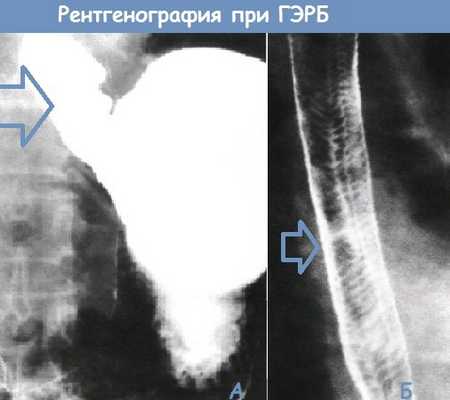

А. Рентгеноконтрастное исследование с барием, демонстрирующее спонтанный гастроэзофагеальный рефлюкс у пациента в горизонтальном положении

Б. Рентгенограмма пищевода с двойным контрастированием. «Кошачий пищевод» с многочисленными тонкими поперечными складками. Данные складки обычно непостоянны и часто сопутствуют ГЭРБ.